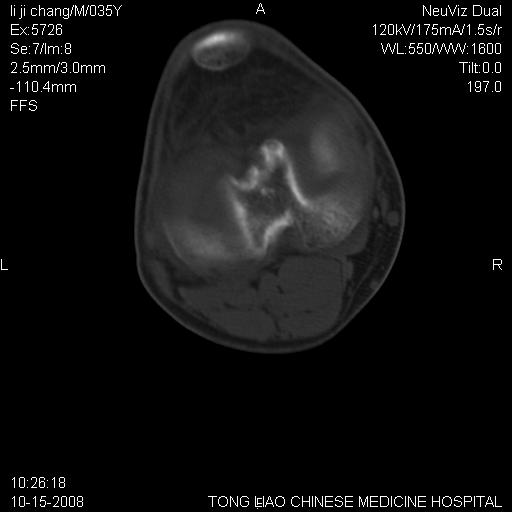

男,35岁,骨科诊断骨性关节炎。继往使用过激素,现股骨头坏死。膝关节病变,请会诊

一元论-----亦考虑为坏死

支持考虑无菌坏死

支持无菌坏死伴退行性骨关节病.

剥脱性骨软骨炎:是一种关节下软骨及软骨下骨缺血性坏死。

支持 无菌性坏死伴退行性骨关节病。